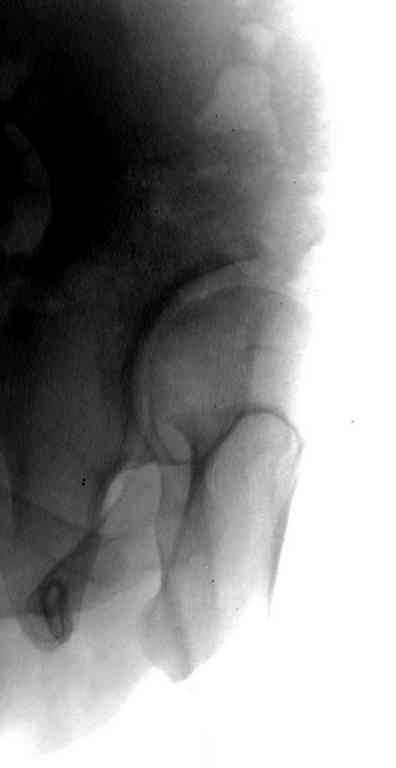

Типичная концовка проигнорированного диспластического состояния сустава. Дисплазия тазобедренного сустава часто встречающаяся патология у жителей Центральной Азии вследствие тугого пеленания в детстве. Традиционно ребенок находится в течение дня в так называемой кроватке "бешик", удобной в быту, но она впоследствии приводит к недоразвитию тазобедренного сустава.

У женщин болезнь клинически проявляется после беременности болями в суставе. Но во время беременности из-за невозможности рентген обследования проблема игнорируется, и упускается время. После беременности симптомы исчезают, и проявляются во время следующей беременности или после увеличения веса.

Данный сустав в начальной стадии разрушения, но все-таки я бы сделал обзорный таз и отдельные снимки сустава в 30 градусной абдукции и аддукции. Также снимки с внутренней и наружной ротацией для оценки состояния головки бедра.